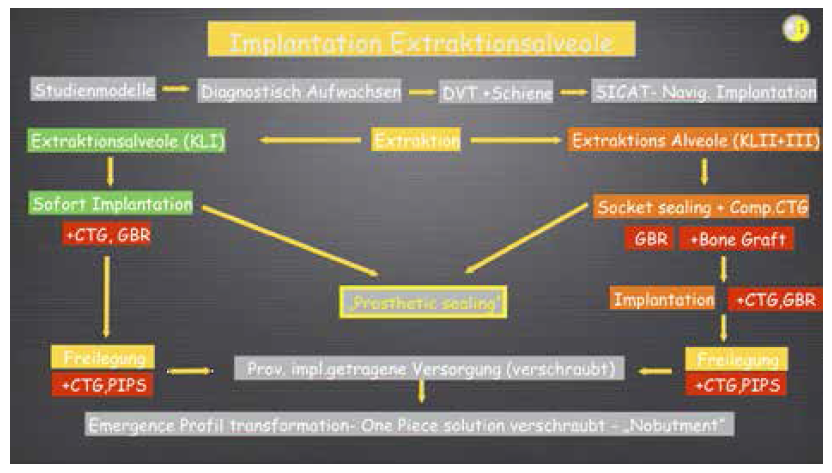

Eine einfache zusätzliche intraoperative Hilfestellung gibt neben der Positionierungsschiene die 3-2 Faustregel, die besagt, dass das gesetzte Implant ca. 3 mm unterhalb und 2 mm innerhalb des „Facial Gingival Margin“, also des bukkalen Gingivarandes gesetzt werden sollte – wobei aber hier natürlich die individuelle Planungsstrategie immer Vorrang haben sollte. Die intraoperativ angewendete Strategie bezüglich der unter Umständen notwendigen Augmentationsmaßnahmen ist in der Grafik Implantation Extraktionsalveole dargelegt.

Abhängig von der Klassifizierung der Extraktionsalveole (I-III) können sowohl Weichgewebsaugmentationen (CTG- Connective Tissue Graft- Bindegewebstransplantat, freies Schleimhauttransplantat FST- und Kombinationstransplantate aus CTG und FST) als auch Hartgewebsaugmentationen (GBRGuided Bone Regeneration, Knochentransplantate) erfolgen. Diese Eingriffe können je nach gewählter Strategie entweder intraimplantationem, bei Freilegung (Periimplant plastic surgery-PIPS) oder aber auch nach Notwendigkeit bei beiden Eingriffen durchgeführt werden.